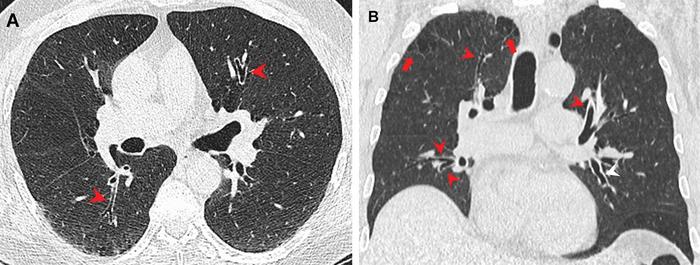

To determine the effects of marijuana and cigarette smoking, researchers for the multicenter prospective study examined the chest CT images of four patient groups: non-smokers, cigarette smokers, marijuana smokers, and combined marijuana and cigarette smokers. Marijuana smokers included in the study had smoked marijuana at least four times a month for two years. Patients who ingested marijuana via edibles or oral drops were excluded from the study.

The researchers found that people who combined marijuana and cigarettes were 12 times more likely to have centrilobular emphysema than non-smokers. Centrilobular emphysema is a type of pulmonary emphysema where the air sacs within the lungs are damaged. This can lead to breathing difficulties and other serious respiratory symptoms.

Combined marijuana and cigarette smokers were three to four times more likely to have airway wall thickening, which can lead to infections, scarring and further airway damage. Association with marijuana only and smoking only with bronchial wall thickening was not as significant. Similar results were seen with centrilobular and paraseptal emphysema, suggesting that the combination of cigarette and marijuana smoking may have a synergistic role on the lungs and airways.